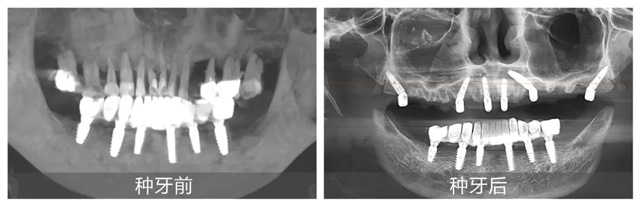

在配備數(shù)字化導(dǎo)板系統(tǒng)的現(xiàn)代化手術(shù)室里,黃杰終于迎來(lái)期盼已久的“試煉場(chǎng)”。短短一年,就已經(jīng)成功種植修復(fù)2100+顆牙,完成無(wú)牙頜即刻負(fù)重手術(shù)110臺(tái)。不僅在種牙數(shù)量上取得了突破,在質(zhì)量方面也同樣出色。